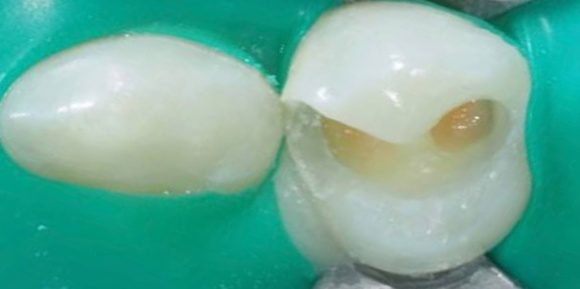

Лечение кариеса